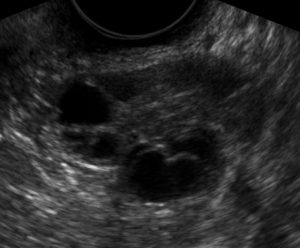

Ovarios poliquísticos

Síndrome de Ovarios Poliquísticos (SOP)